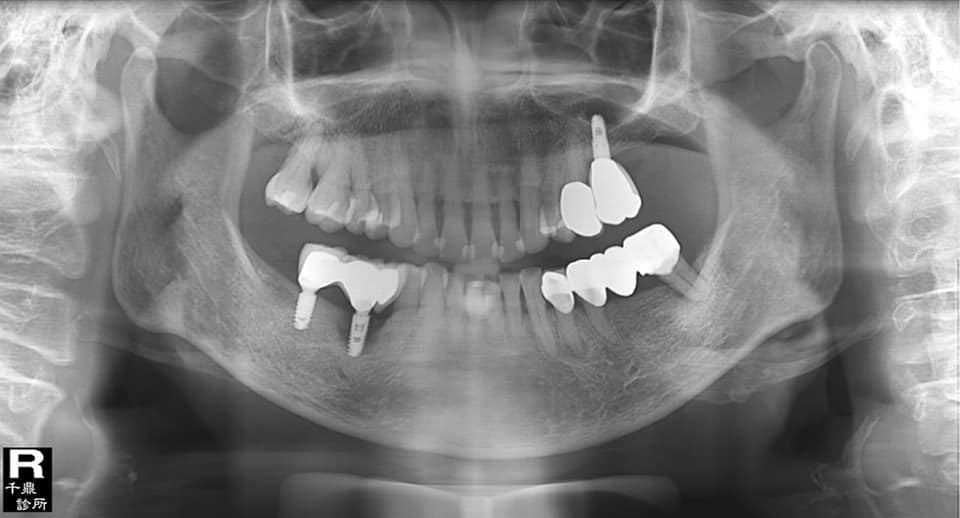

人工牙根則不同,植根表面極度粗糙,在電子顯微鏡下可見充斥著小到10um以下的孔洞,在植體製程中有一道程序叫做「表面處理」,係利用各種化學或物理方法在鈦金屬表面製作凹凸不平的孔洞。這些孔洞的作用,是提供給造骨細胞的偽足更多的表面積和機械力去附著,加速骨整合的進行,原本是極好的設計。但是,如果植體受到感染,這些孔洞卻成為細菌最佳的避難所,而使得植根表面的污染物更難以完全且有效的清除和消毒,療效自然就大打折扣了。

長久以來,植體周圍炎的療效無法預期就是卡在這一關,所以絕大部分的臨床醫師都認為拔掉植根,重新植牙的成功率比治療高。

所幸各種新型器械的應用,如噴砂、雷射甚至最新的電解設備,比較能有效地清潔消毒植根表面而提高治療的成功率。(Petsos 2020, James 2014, Ratka 2020)